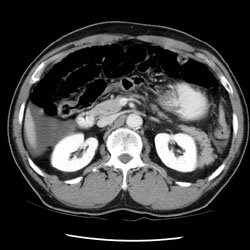

RADIOLOGY: ABDOMEN: Case# 34185

Author

Peter Anderson

abdomen, radiology